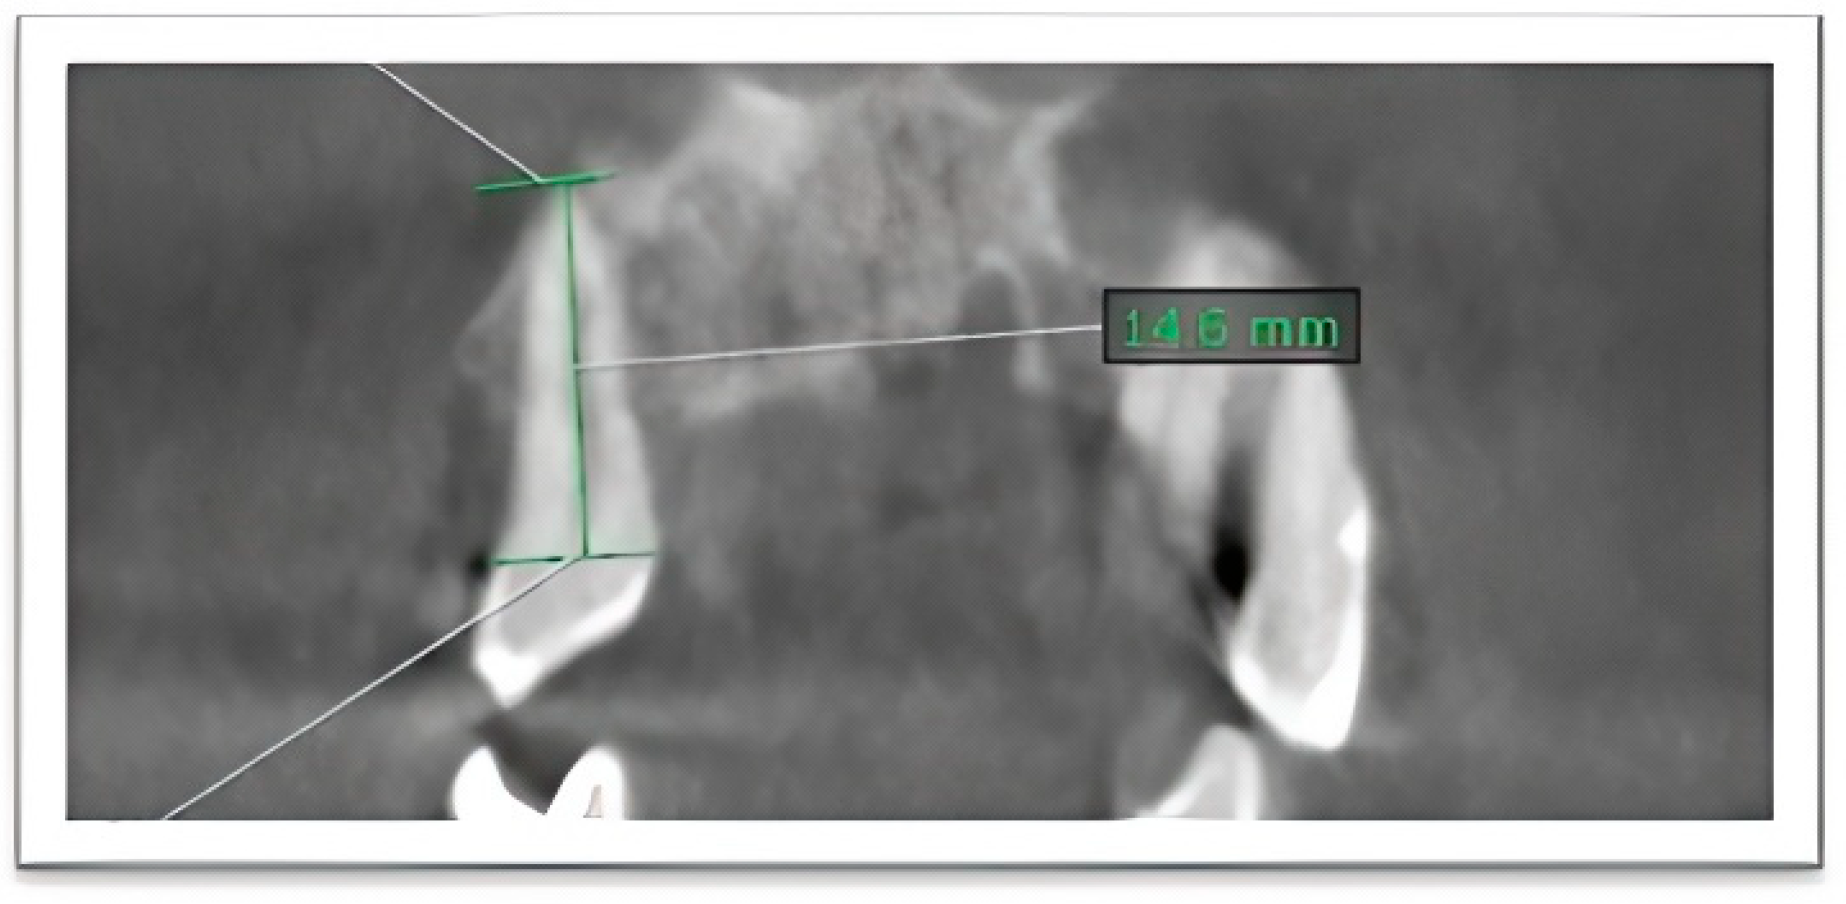

- Root length (coronoapical length) was measured as the linear distance from the midpoint of the CEJ to the most apical point of the root along the long axis of the tooth (Figure 1).